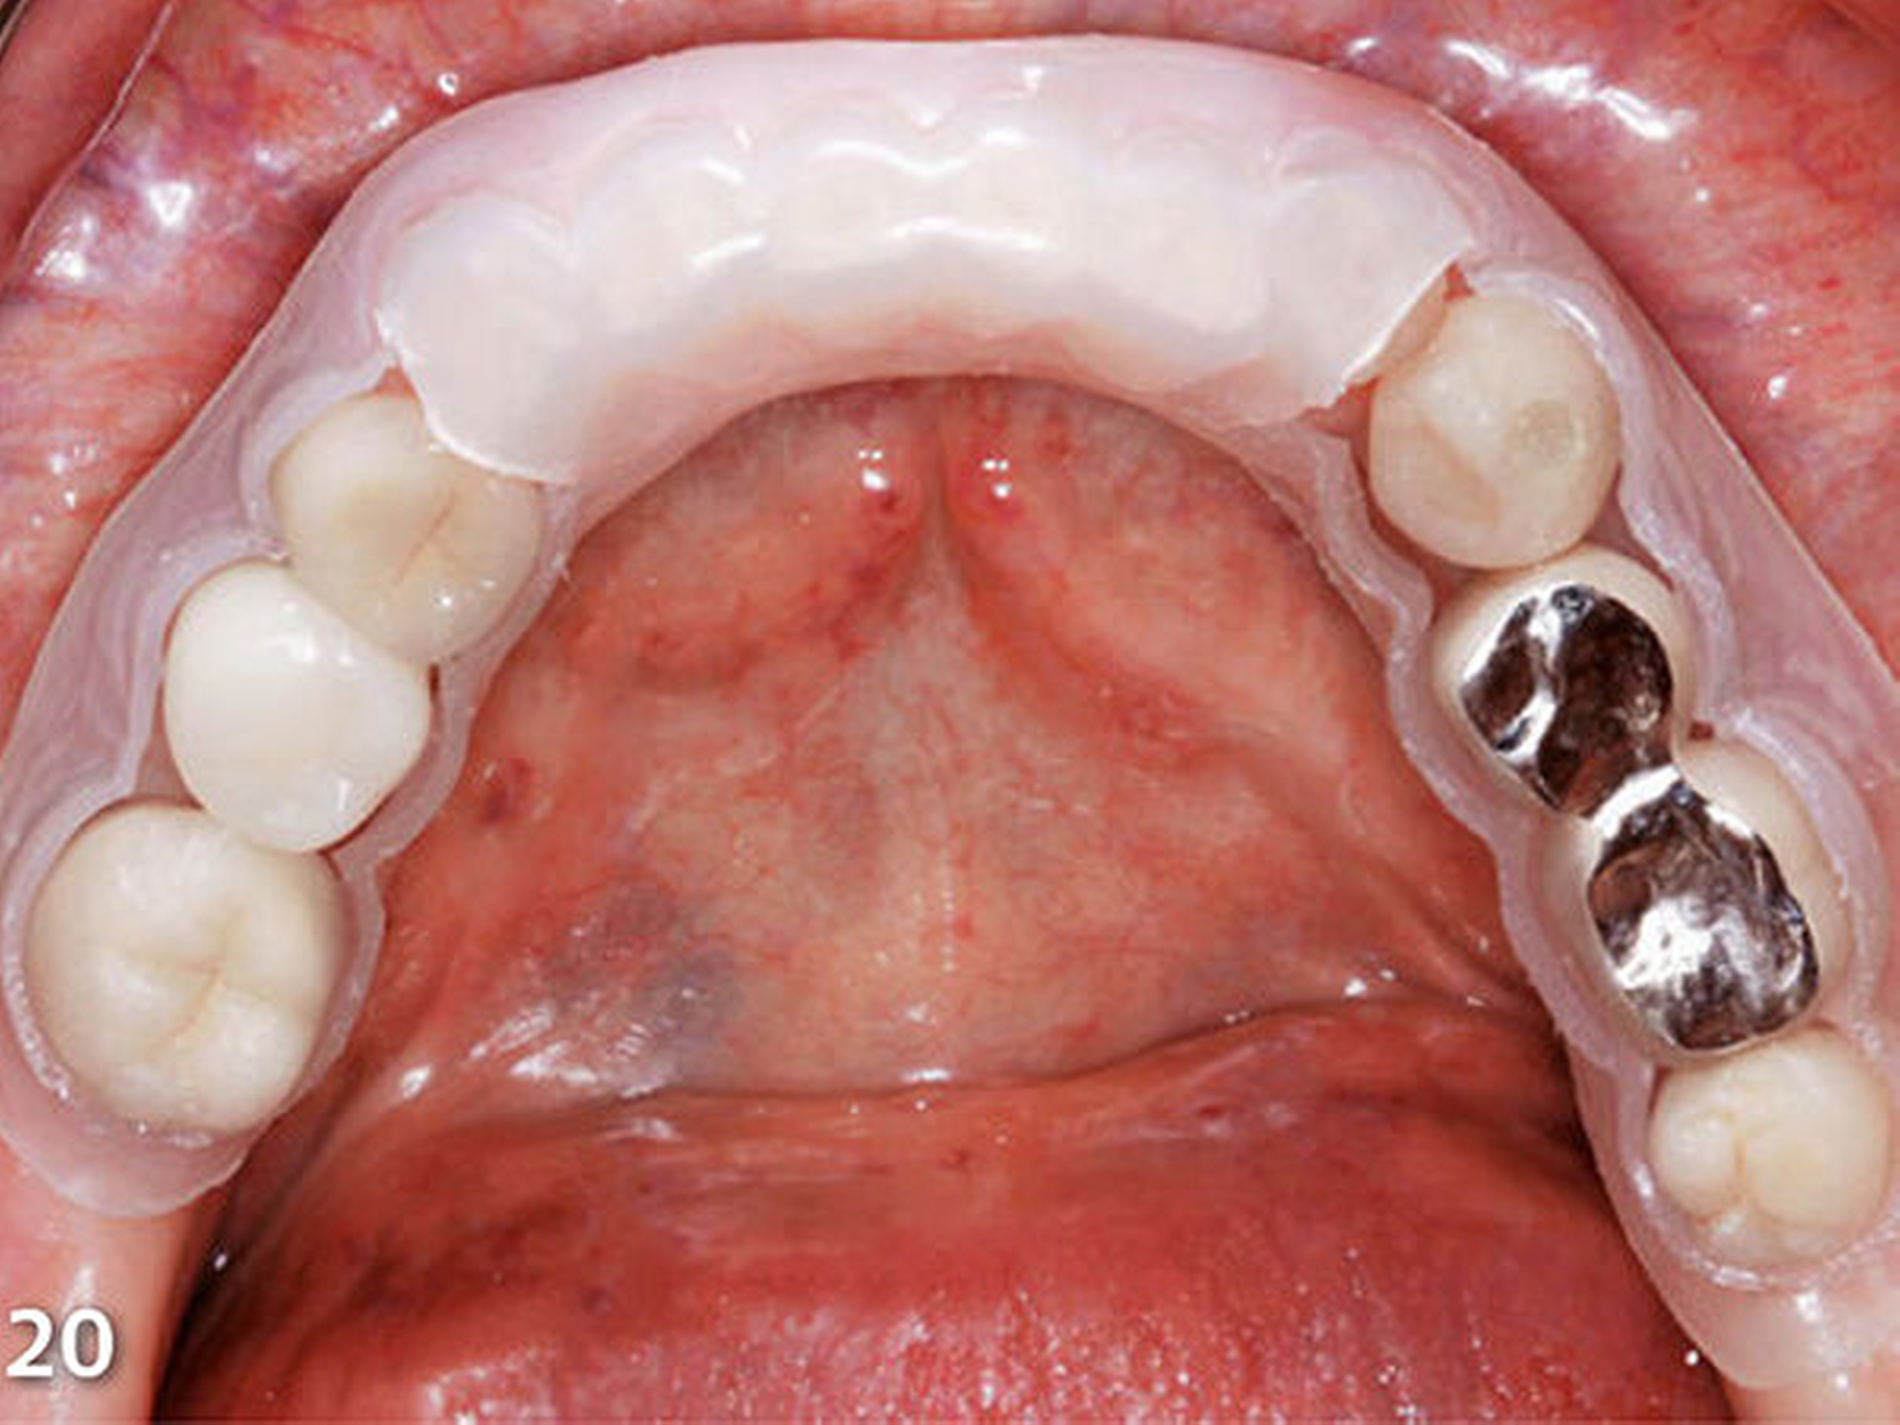

In korrekter Endposition stellt die Schiene die verloren gegangene Zahnhartsubstanz als Hohlraum zwischen Schienenkunststoff und okklusalen Restzahnanteilen dar (Schmidlin et al. 2009c). Nachdem die Schiene zum Schutz der Weichgewebe, an der selektiv die vorzubehandelnden Bereiche freigeschnitten wurden, intraoral positioniert wurde (Abb.20), erfolgte mit einem intraoralen Sandstrahlgerät die tribochemische Silikatisierung (CoJet, 3M Espe) im Bereich der okklusalen Oberflächen der vorhandenen Restaurationen (Abb.21) (Frankenberger et al. 2000, 2014; Matinlinna 2013; Ozcan 2003). Nach Entnahme der Schutzschiene wurde auf die derart silikatisierten Oberflächen sorgfältig ein Silan aufgetragen (Abb.22) (Blatz et al. 2003; Kupiec et al. 1996).

Diese beiden Schritte dienen zum Aufbau einer chemischen Verbindung zwischen den alten Kauflächen aus Metall bzw. Keramik und den nachfolgend einzubringenden neuen Aufbauten aus Komposit. In Vorbereitung zur Applikation des Komposits wurden nachfolgend die silanisierten Oberflächen mit einem Adhäsiv benetzt, welches dünn verblasen und sofort mit Licht polymerisiert wurde. Wenn eine kontaminationsfreie Arbeitsumgebung durch relative Trockenlegung mittels Watterollen bzw. Wangenkissen und effektiver Absaug- bzw. Abhaltetechnik durch eine erfahrene zahnmedizinische Fachassistenz sichergestellt ist, kann bei Adhäsivrestaurationen auf eine absolute Trockenlegung mit Kofferdam verzichtet werden (Brunthaler et al. 2003; Heintze et al. 2015; Opdam et al. 2016; Raskin et al. 2000; Smales 1993; van Dijken & Horstedt 1987).